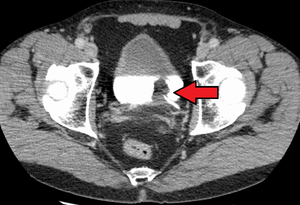

|

Transitional cell carcinoma of the bladder. The white in the bladder is contrast. | |

Bladder cancer is any of several types of cancer arising from the epithelial lining (i.e., the urothelium) of the urinary bladder. Rarely the bladder is involved by non-epithelial cancers, such as lymphoma or sarcoma, but these are not ordinarily included in the colloquial term "bladder cancer." It is a disease in which abnormal cells multiply without control in the bladder.[1]

The most common type of bladder cancer recapitulates the normal histology of the urothelium and is known as transitional cell carcinoma or more properly urothelial cell carcinoma. Five-year survival rates in the United States are around 77%.[2]